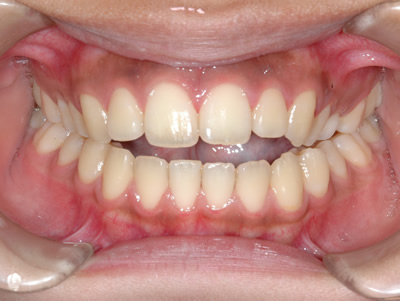

前歯の隙間を気にして来院されました。抜歯はせずにマルチブラケット装置で治療しました。治療期間は1年7ヶ月でした。

初診時

終了時